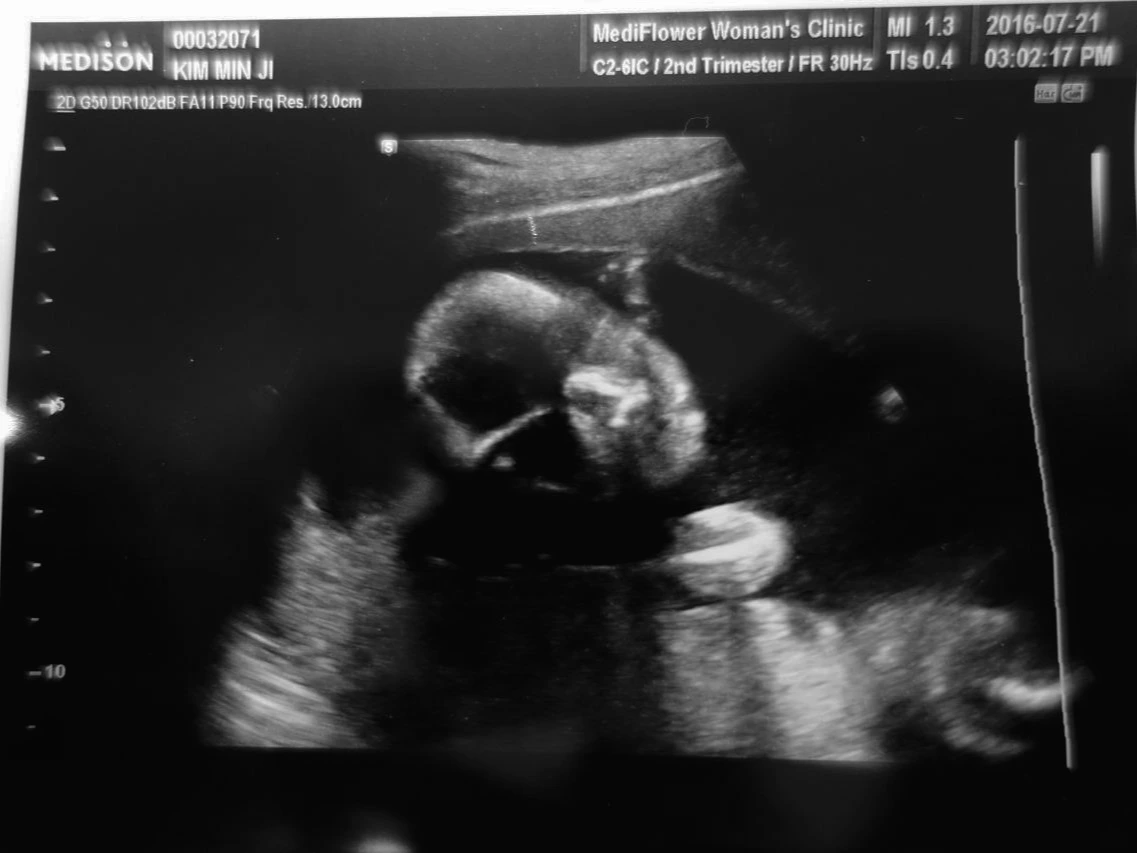

봄이는 머리를 왼쪽 위에, 다리를 오른쪽 아래에 두고 있었다. 정밀 초음파라 그런지 보이는 디테일이 달랐다. 척추가 둥그렇게 휘어있고 그 아래로 갈비뼈가 날개깃처럼 달려있다. 손가락 마디마디가 보이고 살짝 오므린 손아귀가 보인다. 길쪽한 팔 뼈와 허벅지 뼈가 단단해 보인다. 심장은 2심방 2심실이 뚜렷이 구분되어 보이고, 좌뇌 우뇌 공간도 무사히 채워져가고 있다. 양말을 매번 구멍 내는 내 둘째 발가락을 닮았나 자세히 보지는 못했지만 왼발, 오른발 모두 귀엽게 잘 있었다. 콧대가 생겼고 콧구멍도 뚫려있다. 입술 라인이 생겼고 귀도 모양을 갖췄다. 위와 간을 비롯한 주요 장기들이 있을 곳에 자리를 잡고 있었다. 초음파를 봐준 선생님이 길이를 잰다. 머리 끝에서 엉덩이까지 15cm. 내 엄지에서 검지를 쭉 뻗은 거리보다 작은 공간에 봄이가 들어온다. 15cm 안에 눈, 코, 귀, 입, 어깨, 팔, 손, 손가락, 다리, 발, 발가락, 엉덩이, 허리를 갖춘 봄이가 있다.

DSC04565.JPG 생애 최초 정면샷

눈을 감고 있는 봄이는 손을 오므렸다 피고 등을 구부렸다 피고 다리를 접었다 눕히고 한시도 가만히 있질 않았다. 선생님은 자기를 안 도와준다며 투정 아닌 투정을 부렸지만 나는 흐뭇하기만 했다. 한편으로 의아하기도 했다. 아내와 나 둘 다 엄청 활발한 타입은 아닌데 어쩐 일이지? 이러니 저러니 활발하게 꼼지락거리는 봄이의 모습을 보니 살짝 전율이 일었다. 15cm의 작은 기적이다.